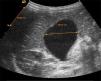

Se describe el caso de un niño de 2 años, sin antecedentes de interés, que consulta por vómitos, fiebre y deposiciones diarreicas de 3 días de evolución. Al ingreso presenta un estado de hidratación conservado, afebril, irritabilidad ante la manipulación, auscultación cardiorrespiratoria normal. El abdomen se muestra distendido, blando, depresible y sin megalias, con peristalsis aumentada. A nivel del cuadrante superior derecho del abdomen se palpa una masa dolorosa de consistencia blanda, bien delimitada y tamaño aproximado de 5cm de diámetro. En la analítica de ingreso destaca ligera elevación de la aspartato aminotransferasa: 68 U/l y de la proteína C reactiva: 12mg/l. La detección del antígeno de rotavirus en heces fue positiva. La ecografía abdominal muestra una vesícula biliar distendida con contenido espeso en su interior, sin dilatación de la vía biliar (fig. 1). Se instaura perfusión glucosalina, dieta absoluta y analgesia. A partir del tercer día del ingreso, se aprecia una mejoría clínica significativa con leve molestia a la palpación a nivel subcostal derecho; en la ecografía abdominal de control, se evidencia una disminución significativa del volumen de la vesícula biliar (fig. 2). El paciente recibe el alta hospitalaria y al mes se realiza un control ambulatorio, permaneciendo asintomático y con ecografía abdominal normal.

La ecografía abdominal sigue siendo la prueba de elección en el diagnóstico de esta entidad, donde se observa la vesícula biliar distendida, en ausencia de cálculos y patología del árbol biliar. En ocasiones, puede ser útil el estudio de imagen que dibuja el árbol hepatobiliar usando Tc 99 marcado con ácido diaminoacético; este marcador presenta una rápida excreción biliar con acúmulo de la radiactividad a nivel de la vesícula biliar y puede ser de ayuda en la confirmación diagnóstica, pero no es esencial10.